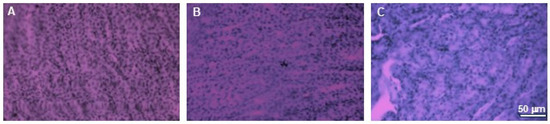

2.2. Histopathological Studies

3.3. Histopathological Studies